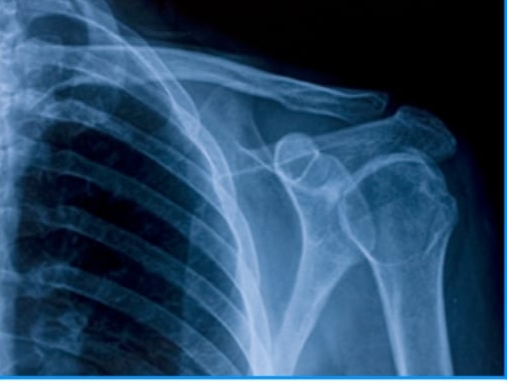

Hydroxyapatite: is a naturally occurring mineral form of calcium apatite, it is a hydrated calcium phosphate with chemical formula of (Ca5(PO4)3(OH)) similar to the human hard tissues in the morphology and composition. The OH- ions can be replace by fluoride, chloride or carbonate to produce fluroapatite or chlorapatite. HA crystallizes in the hexagonal system. The pure HA is white, can also have brown, yellow, or green colorations. <br />An important character of HA is its stability when compared to the other calcium phosphate, it is the most stable calcium phosphate compound under physiological conditions as temperatures, pH and composition of body's fluids. Bone and teeth enamel are largely composed of a form of this mineral.<br />Nano – Hydroxyapatite (Nano – HA) is very attractive as biomaterial for use in the prosthetic applications due to the high similarity in the size, crystallography, and chemical composition with human hard tissues.<br />Key Properties of HA: <br />1- The ability to react in bone structures and support bone growth, without breaking down or dissolving (bioactive), and result in healing times shorter than those observed if HA was not used. <br /><br />2- Non toxicity and non inflammatory nature <br />3- Biocompatibility <br />4- Osteoconductivity<br /><br />Applications:<br />1- Bioceramic Coating: coats made from hydroxyapatite are often applied to metallic implants such as (Titanium/Titanium alloys) or (Stainless steel) to alter surface nature, in the case the body will be happy to accept, without any negative reaction. <br />2- Bone Filler: HA may be applied in the form of powder, porous blocks or beads to fill bone defects or voids. <br />3- HA is increasingly used to make bone grafting materials as well as dental prosthetics and repair. Some implants, e.g. hip replacements, dental implants and bone conduction implants, are coated with HA. As the native dissolution rate of HA in vivo, around 10 wt% per year, is significantly lower than the growth rate of newly formed one tissue, in its use as a one replacement material, ways are being sought to enhance its stability rate and thus promote better bioactivity. <br />4- Nano – Hydroxyapatite is the main component of enamel, it gives a bright white appearance and eliminates the light reflectivity by closing the small voids of the enamel surface.<br />5- Nano – Hydroxyapatite very useful in the repairing of enamel by incorporating it in toothpastes and mouth – rinsing solution to promote the restoration of deminerallized enamels or dentin surface by depositing HA nano-particles in the defects. <br /><br />6- HA ceramics has been widely applied as bone substitutes together with β- tricalcium phosphate or with bio – polymer because their chemical <br /><br /><br />composition close to the mineral phase of bone is an origin of their excellent biocompatibility to tissue bone. <br /><br />HA/Polymer composite for bone grafting<br /><br />Hedrogel/HA composite, which has a mineral/organic matrix ratio approximating that of human bone<br />7- Early carious lesions treatment <br />8- Drug and gene delivery <br />9- Edentulous ridge augmentation<br />10- Endodontic treatment like pulp capping<br /><br /><br />11- Recently, experimental nano structured composite air filters containing HA were found to be efficient in absorbing CO, which lead to its use in reducing automotive exhaust pollutants